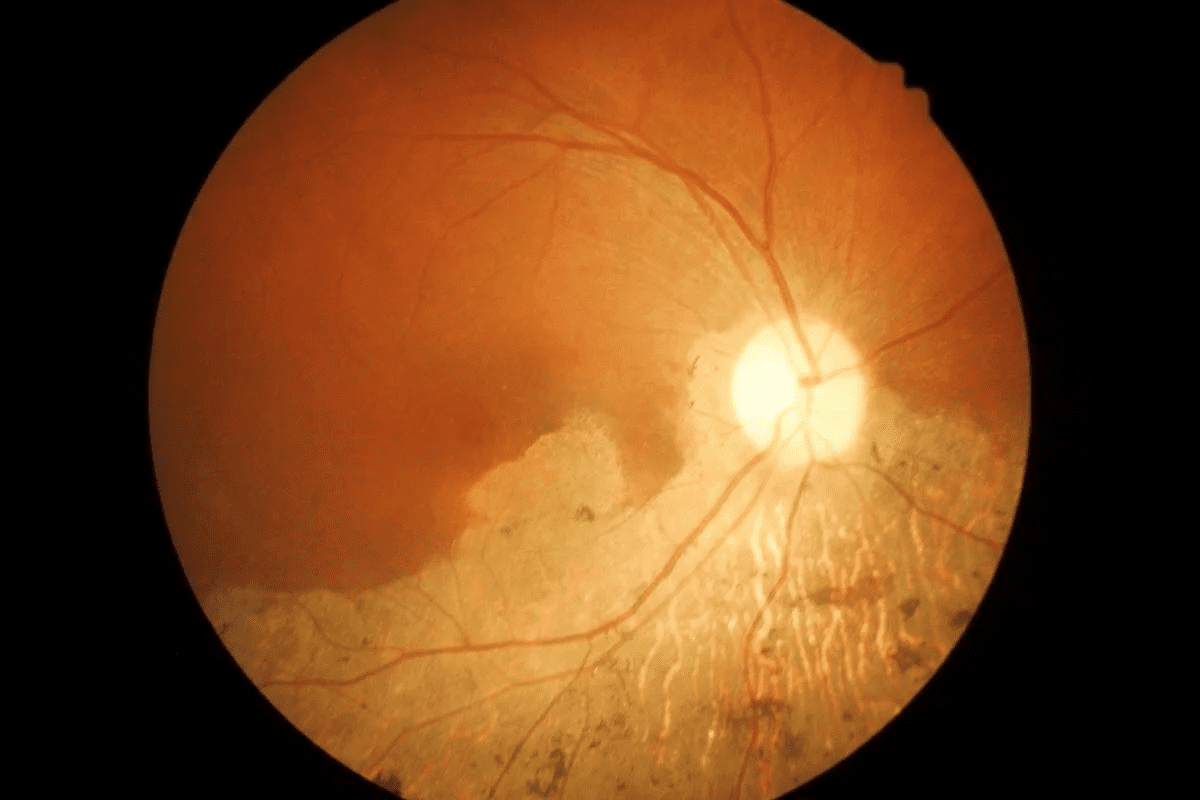

Macular degeneration affects the macula, key for central vision and detail. It’s a leading cause of vision loss in older adults. There are two types: dry AMD, with debris under the macula, and wet AMD, with abnormal blood vessels.

Hydroxychloroquine and Chloroquine Toxicity

Hydroxychloroquine and chloroquine have been used for years. But, long-term use can damage the retina. This damage can cause permanent vision loss.

The risk of this damage depends on the dose and how long you take the drug. Studies show a high risk of retinal damage after five years of use.

“The risk of hydroxychloroquine retinopathy is low within the first five years of use, but it rises sharply after that,” as noted by medical professionals. This highlights the importance of regular monitoring for patients on long-term antimalarial therapy.